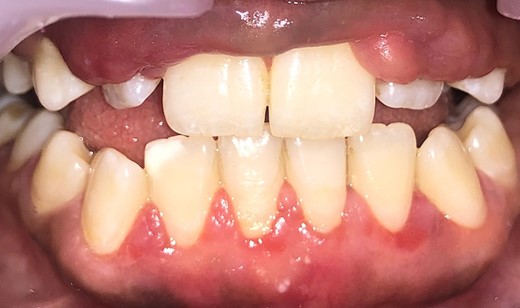

Intraoral examination shows generalized puffiness and swollen gingiva, mainly in the upper and lower anterior region covering two-third of the entire teeth, the color of the gingiva was bluish red, which bleeds on slight provocation as well as on mastication of hard food. (Fig. 1).